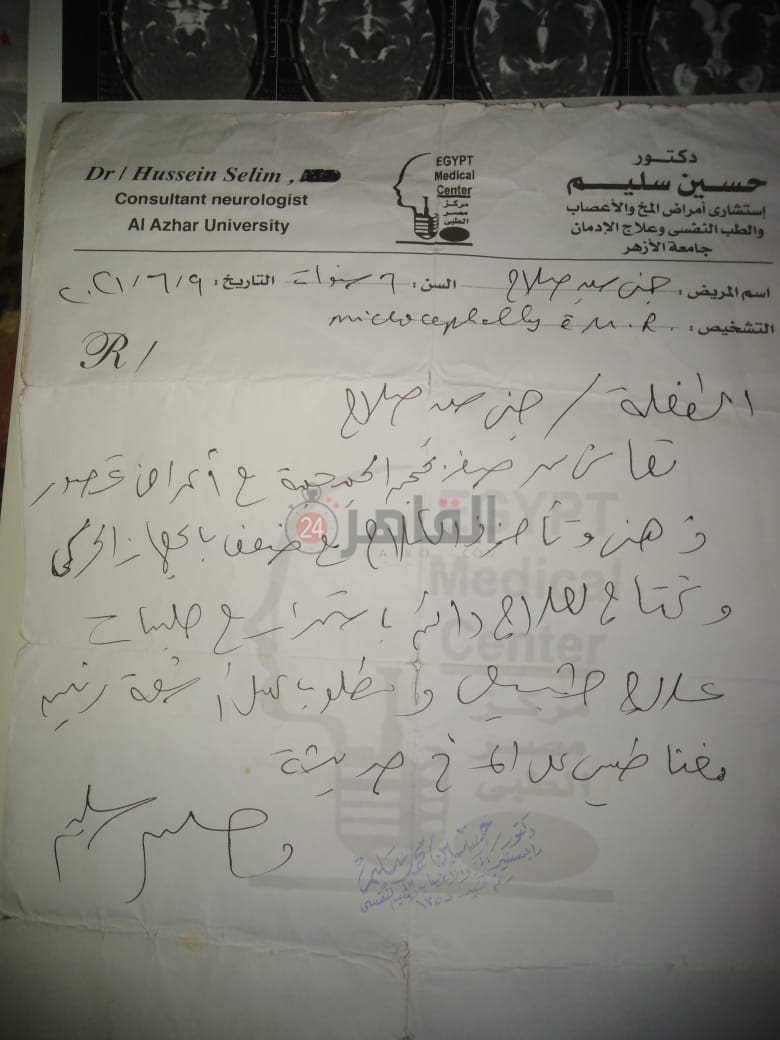

من جانبه، قال صلاح سيد، والد الطفلة جنى صلاح، إن ابنته تعاني من ضمور في المخ منذ ولادتها، نتيجة خطأ طبي، أدى إلى نقص كبير في الأكسجين لديها.

وأضاف في تصريحات خاصة لـ "القاهرة 24": "جنى تبلغ من العمر 6 سنوات، لا تستطيع المشي أو الوقوف على قدميها، نتيجة إصابتها بضمور في المخ منذ ولادتها".

وتابع: "مكنتش بتتحرك خالص، وجسمها طري، روحت كشفت عليها، وعملت أشعة وتحاليل كتير، أتأكدنا إصابتها بضمور في المخ"، مضيفًا:" مش بتعرف تأكل احنا اللي بنأكلها، هي عقلها كويس لكن مش بتتحرك ولا تتكلم".

وأوضح أن الطبيب الخاص بها أكد أن هناك داء خارج مصر يحسن من حالتها، ولكن باهظ الثمن، وتحتاج تناوله بشكل دوري.

واستكمل:" حاليًا تتناول أدوية شرب عادية، لحين توفيرالدولة علاجها من خارج مصر"، مشيرًا: "مفعتش قضية على الدكتور، ورضيت بقضاء ربنا".